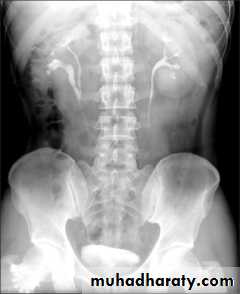

*Phlebolith (arrow):-round lucent centre,,it represents calcified thrombus in pelvic vein.